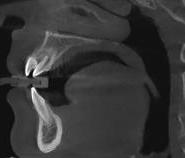

Estudios radiográficos de inicio

Al análisis radiográfico (Figura 3) se observa la clase II esquelética, patrón de crecimiento normodivergente, incisivo superior con adecuada inclinación respecto a su base ósea, incisivo inferior ligeramente proinclinado y vías aéreas permeables. En la radiografía panorámica (Figura 4) se ven 33 órganos dentarios OD, el infantil 53 presente en boca, el OD 13 impactado, los 37 y 47 en proceso de erupción y los terceros molares en formación.

En los cortes tomográficos, en el corte coronal (Figura 5) se muestra el OD 13 impactado y su proximidad con el incisivo lateral, en el corte sagital (Figura 6) grado de reabsorción radicular del OD 12.